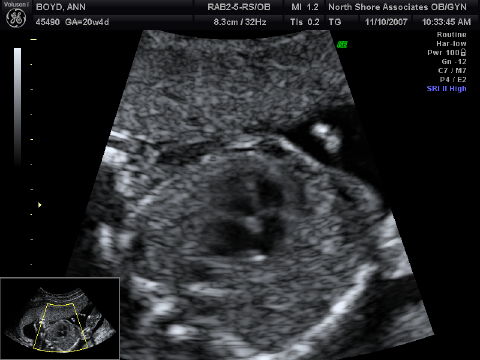

{"id":1479,"date":"2007-11-10T13:02:03","date_gmt":"2007-11-10T19:02:03","guid":{"rendered":"http:\/\/boydsnest.org\/news\/2007\/and-its-a\/"},"modified":"2007-11-10T13:02:03","modified_gmt":"2007-11-10T19:02:03","slug":"and-its-a","status":"publish","type":"post","link":"https:\/\/boydsnest.org\/news\/2007\/and-its-a\/","title":{"rendered":"And it&#8217;s a&#8230;"},"content":{"rendered":"<p>We&#8217;ve just come back from the midwives&#8217; office, where we had our midterm ultrasound. That means that, at 20+ weeks, Belly Baby is just about half-baked  &#8212;  and plenty developed for modern technology to take a peek at the private parts. We sure were curious! And now we&#8217;re pleased to announce that it&#8217;s a&#8230; <!--more--><\/p>\n<p><img src='http:\/\/boydsnest.org\/news\/wp-content\/uploads\/2007\/11\/boyd-baby_13-crop.jpg' alt='And it\u00e2\u20ac\u2122s a\u00e2\u20ac\u00a6' class=\"alignright\" \/><\/p>\n<p>*Girl!* And here she is, shyly peeking out from behind her placenta.<\/p>\n<p>Hooray! We really like girls (especially Papa), so this is very happy news. Not that there&#8217;s anything wrong with being a boy (especially Papa), and we have plenty of boy friends (especially Papa). But it&#8217;s quite easy for us to rejoice in this news of a little sister for Lucy and another daughter for us.<\/p>\n<p>On the other hand, we&#8217;re pretty sure we don&#8217;t want to follow in &#8220;the Bennets&#8217; footsteps&#8221;:http:\/\/en.wikipedia.org\/wiki\/Pride_and_Prejudice#Mr._Bennet and end up with five marriageable sisters in the family. Especially Papa.<\/p>\n<div style=\"clear:both;\"><\/div>\n<p>*More Ultrasound Snaps*<\/p>\n<p>Here are a couple more, selected shots of her:<\/p>\n<p><img src='http:\/\/boydsnest.org\/news\/wp-content\/uploads\/2007\/11\/boyd-baby_11-crop.jpg' alt='Another 3D' class=\"alignleft\" \/><\/p>\n<p>Photo: Another three-dimensional shot. We got more of these, but (as often happens for midterm ultrasounds) they look more than a little skeletal  &#8212;  and we didn&#8217;t want to unduly frighten any sensitive viewers. :)<\/p>\n<p>(Speaking of which, the apparent gaps in the top of her head, visible in these first two photos, are perfectly normal at this stage. Remember, it&#8217;s a big brain we humans have, and it&#8217;s gotta get out during birth, so the skull stays flexible all the way through gestation.)<\/p>\n<div style=\"clear:both;\"><\/div>\n<p>Want proof that Belly Baby is in fact a mammal? Here&#8217;s a cross-section of her fully functioning &#8220;four-chambered heart&#8221;:http:\/\/www.lyricstime.com\/they-might-be-giants-mammal-lyrics.html:<\/p>\n<p><img src='http:\/\/boydsnest.org\/news\/wp-content\/uploads\/2007\/11\/boyd-baby_6.jpg' alt='Large Four-Chambered Heart' \/><\/p>\n<p>And finally, here&#8217;s a portrait, showing her opening her mouth really wide  &#8212;  getting ready to holler loud enough to be heard over Lucy, I suppose!<\/p>\n<p><img src='http:\/\/boydsnest.org\/news\/wp-content\/uploads\/2007\/11\/boyd-baby_5.jpg' alt='Big mouth' \/><\/p>\n<p>Go, Baby Girl! We can&#8217;t wait to welcome you to the Big Outdoors!<\/p>\n","protected":false},"excerpt":{"rendered":"<p>We&#8217;ve just come back from the midwives&#8217; office, where we had our midterm ultrasound. That means that, at 20+ weeks, Belly Baby is just about half-baked &#8212; and plenty developed for modern technology to take a peek at the private parts. We sure were curious! And now we&#8217;re pleased to announce that it&#8217;s a&#8230;<\/p>\n","protected":false},"author":1,"featured_media":0,"comment_status":"open","ping_status":"closed","sticky":false,"template":"","format":"standard","meta":{"footnotes":""},"categories":[2],"tags":[],"class_list":["post-1479","post","type-post","status-publish","format-standard","hentry","category-kids"],"_links":{"self":[{"href":"https:\/\/boydsnest.org\/news\/wp-json\/wp\/v2\/posts\/1479","targetHints":{"allow":["GET"]}}],"collection":[{"href":"https:\/\/boydsnest.org\/news\/wp-json\/wp\/v2\/posts"}],"about":[{"href":"https:\/\/boydsnest.org\/news\/wp-json\/wp\/v2\/types\/post"}],"author":[{"embeddable":true,"href":"https:\/\/boydsnest.org\/news\/wp-json\/wp\/v2\/users\/1"}],"replies":[{"embeddable":true,"href":"https:\/\/boydsnest.org\/news\/wp-json\/wp\/v2\/comments?post=1479"}],"version-history":[{"count":0,"href":"https:\/\/boydsnest.org\/news\/wp-json\/wp\/v2\/posts\/1479\/revisions"}],"wp:attachment":[{"href":"https:\/\/boydsnest.org\/news\/wp-json\/wp\/v2\/media?parent=1479"}],"wp:term":[{"taxonomy":"category","embeddable":true,"href":"https:\/\/boydsnest.org\/news\/wp-json\/wp\/v2\/categories?post=1479"},{"taxonomy":"post_tag","embeddable":true,"href":"https:\/\/boydsnest.org\/news\/wp-json\/wp\/v2\/tags?post=1479"}],"curies":[{"name":"wp","href":"https:\/\/api.w.org\/{rel}","templated":true}]}}